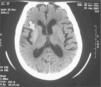

CASO CLÍNICOSe trata de una mujer de 95 años natural de Burgos, sin antecedentes personales ni familiares de interés, que acudió al servicio de urgencias por presentar movimientos anormales en el hemicuerpo izquierdo de 48h de evolución. En los últimos 10 días había notado poliuria, polidipsia y prurito vaginal. No refería traumatismos craneoencefálicos previos ni datos de infección. En la exploración física se detectaron signos de deshidratación cutáneo-mucosa y movimientos anormales, continuos e irregulares en el brazo y la pierna izquierdos. El brazo izquierdo presentaba múltiples hematomas. La cifra tensional era normal. En la analítica realizada se detectó glucemia de 500mg/dl. La gasometría venosa, el hemograma, la bioquímica, el sistemático de orina, el urocultivo, el electrocardiograma y la radiografía de tórax fueron normales. Los cuerpos cetónicos en orina fueron negativos. El cultivo del exudado vaginal fue positivo para Candida sp. En la tomografía computarizada (TC) craneal se detectó un aumento de densidad en el putamen derecho que podría corresponder a una hemorragia petequial en esa zona (fig. 1). La paciente no seguía controles médicos habituales, por lo que fue imposible determinar el tiempo de evolución previa de su diabetes mellitus.

Cuando la hemicorea-hemibalismo se relaciona con el SHNC se detecta una hiperintensidad en el putamen contralateral en la TC craneal y en secuencias potenciadas en T1 de la resonancia magnética (RM). La etiología de esta hiperintensidad es todavía objeto de debate. Debido a que la presentación clínica es aguda y que el núcleo estriado corresponde al territorio vascular de la arteria lenticuloestriada, se ha propuesto que la causa puede ser una hemorragia petequial en esa zona3-5. Sin embargo, la biopsia de una muestra de putamen reveló únicamente la existencia de astrocitos y vacuolización sin restos de hemosiderina6. En estudios en los que se ha empleado la tomografía computarizada por emisión monofotónica (SPECT) y la tomografía por emisión de positrones (PET), se ha objetivado una disminución del flujo sanguíneo y de la actividad metabólica en el núcleo estriado contralateral7,8. Por ello, otra teoría afirma que es la hipofunción del putamen contralateral lo que explicaría tanto la clínica como la neuroimagen. En nuestro caso la hiperintensidad en el putamen derecho fue interpretada por los radiólogos como una hemorragia petequial, si bien a la luz de los estudios anteriormente referidos, este punto no está claro. Hay un número muy limitado de casos publicados de hemicorea-hemibalismo en relación con SHNC9. Suelen ser pacientes diabéticos ancianos con una media de edad de presentación de 72 años9. De hecho, la edad de presentación de hemicorea-hemibalismo en relación con SHNC es mayor que la causada por lesiones vasculares focales, que oscila entre los 61 años del grupo de Dewey1 y los 67 años del grupo de Klawans10. La incidencia es igual en ambos sexos. La mayor parte de los casos publicados se han producido en asiáticos. Podría haber una influencia racial, aunque se requieren más estudios para poder confirmar este punto. Puede ser la forma de presentación de una diabetes mellitus, como fue en este caso. La evolución suele ser buena11 con desaparición de la clínica tras normalización de la glucemia y de la imagen radiológica tras 3-11 meses de evolución12-14.